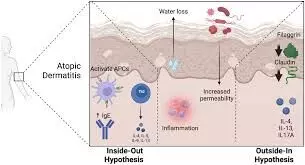

Researchers have found in a new systematic review and meta-analysis that higher levels of environmental pollutants and temperature extremes are associated with an increased population burden of atopic dermatitis. The findings of the study published in the journal of American Medical Association suggest that mitigating pollution and climate change could lead to improved outcomes for individuals with atopic dermatitis.

Climate change and pollution are major health threats that have the potential to worsen the burden of common diseases, such as atopic dermatitis, that are affected by the environment. A study was done to summarize and assess the certainty of evidence on associations between environmental factors and atopic dermatitis outcomes. Studies included observational studies (cohort, case-control, and cross-sectional) that assessed the association observational studies that assessed associations between climate conditions (eg, ambient air pollution, weather, and climate) and atopic dermatitis outcomes in adults 18 years and older. Searches combined Medical Subject Heading terms and keywords for atopic dermatitis and each environmental factor, with no language, date, or geographical restrictions. Data were synthesized using random-effects models, with pooled estimates reported alongside 95% CIs, and the Grading of Recommendations Assessment, Development, and Evaluation was used to assess the certainty of the evidence across outcomes. Results Of 11 402 citations identified, 42 studies were included. There was an increase in atopic dermatitis outpatient clinic visits for every 10-μg/m3 increase in particulate matter 10 μm in diameter or less (risk ratio [RR], 1.008; 95% CI, 1.003-1.012; high certainty), particulate matter 2.5 μm in diameter or less (RR, 1.013; 95% CI, 0.999-1.027; moderate certainty), sulfur dioxide (RR, 1.029; 95% CI, 1.020-1.039; high certainty), and nitrogen dioxide (RR, 1.014; 95% CI, 0.999-1.030; moderate certainty). Extreme environmental temperatures (hot and cold) were are associated with increased atopic dermatitis–related clinical visits (moderate to high certainty). Higher precipitation, including rain, may be associated with increased atopic dermatitis severity (low certainty), and higher levels of humidity are probably associated with increased atopic dermatitis severity (moderate certainty). Increased duration of sunlight exposure had an uncertain association with atopic dermatitis severity (very low certainty). Secondhand smoking exposure and traffic and industrial plant exposure are probably associated with increased atopic dermatitis prevalence (moderate certainty). The results of this systematic review and meta-analysis suggest that increased levels of environmental pollutants and temperature extremes are associated with increased population burden of atopic dermatitis. Measures to mitigate pollution and climate change may improve atopic dermatitis outcomes.